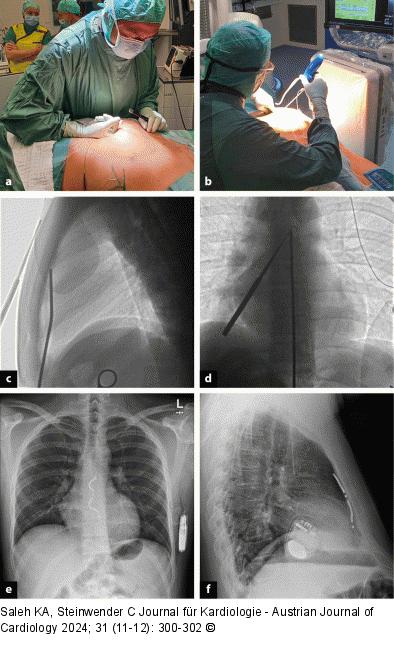

Abbildung 1: Dissektion (a): Blunt Finger Dissection; (b–d): Schrittweise Tunnelierung unter lateraler Fluoroskopie – Bestätigung der Orientierung in ap; (e, f): Thoraxröntgen ap + seitlich |

(a): Blunt Finger Dissection; (b–d): Schrittweise Tunnelierung unter lateraler Fluoroskopie – Bestätigung der Orientierung in ap; (e, f): Thoraxröntgen ap + seitlich |